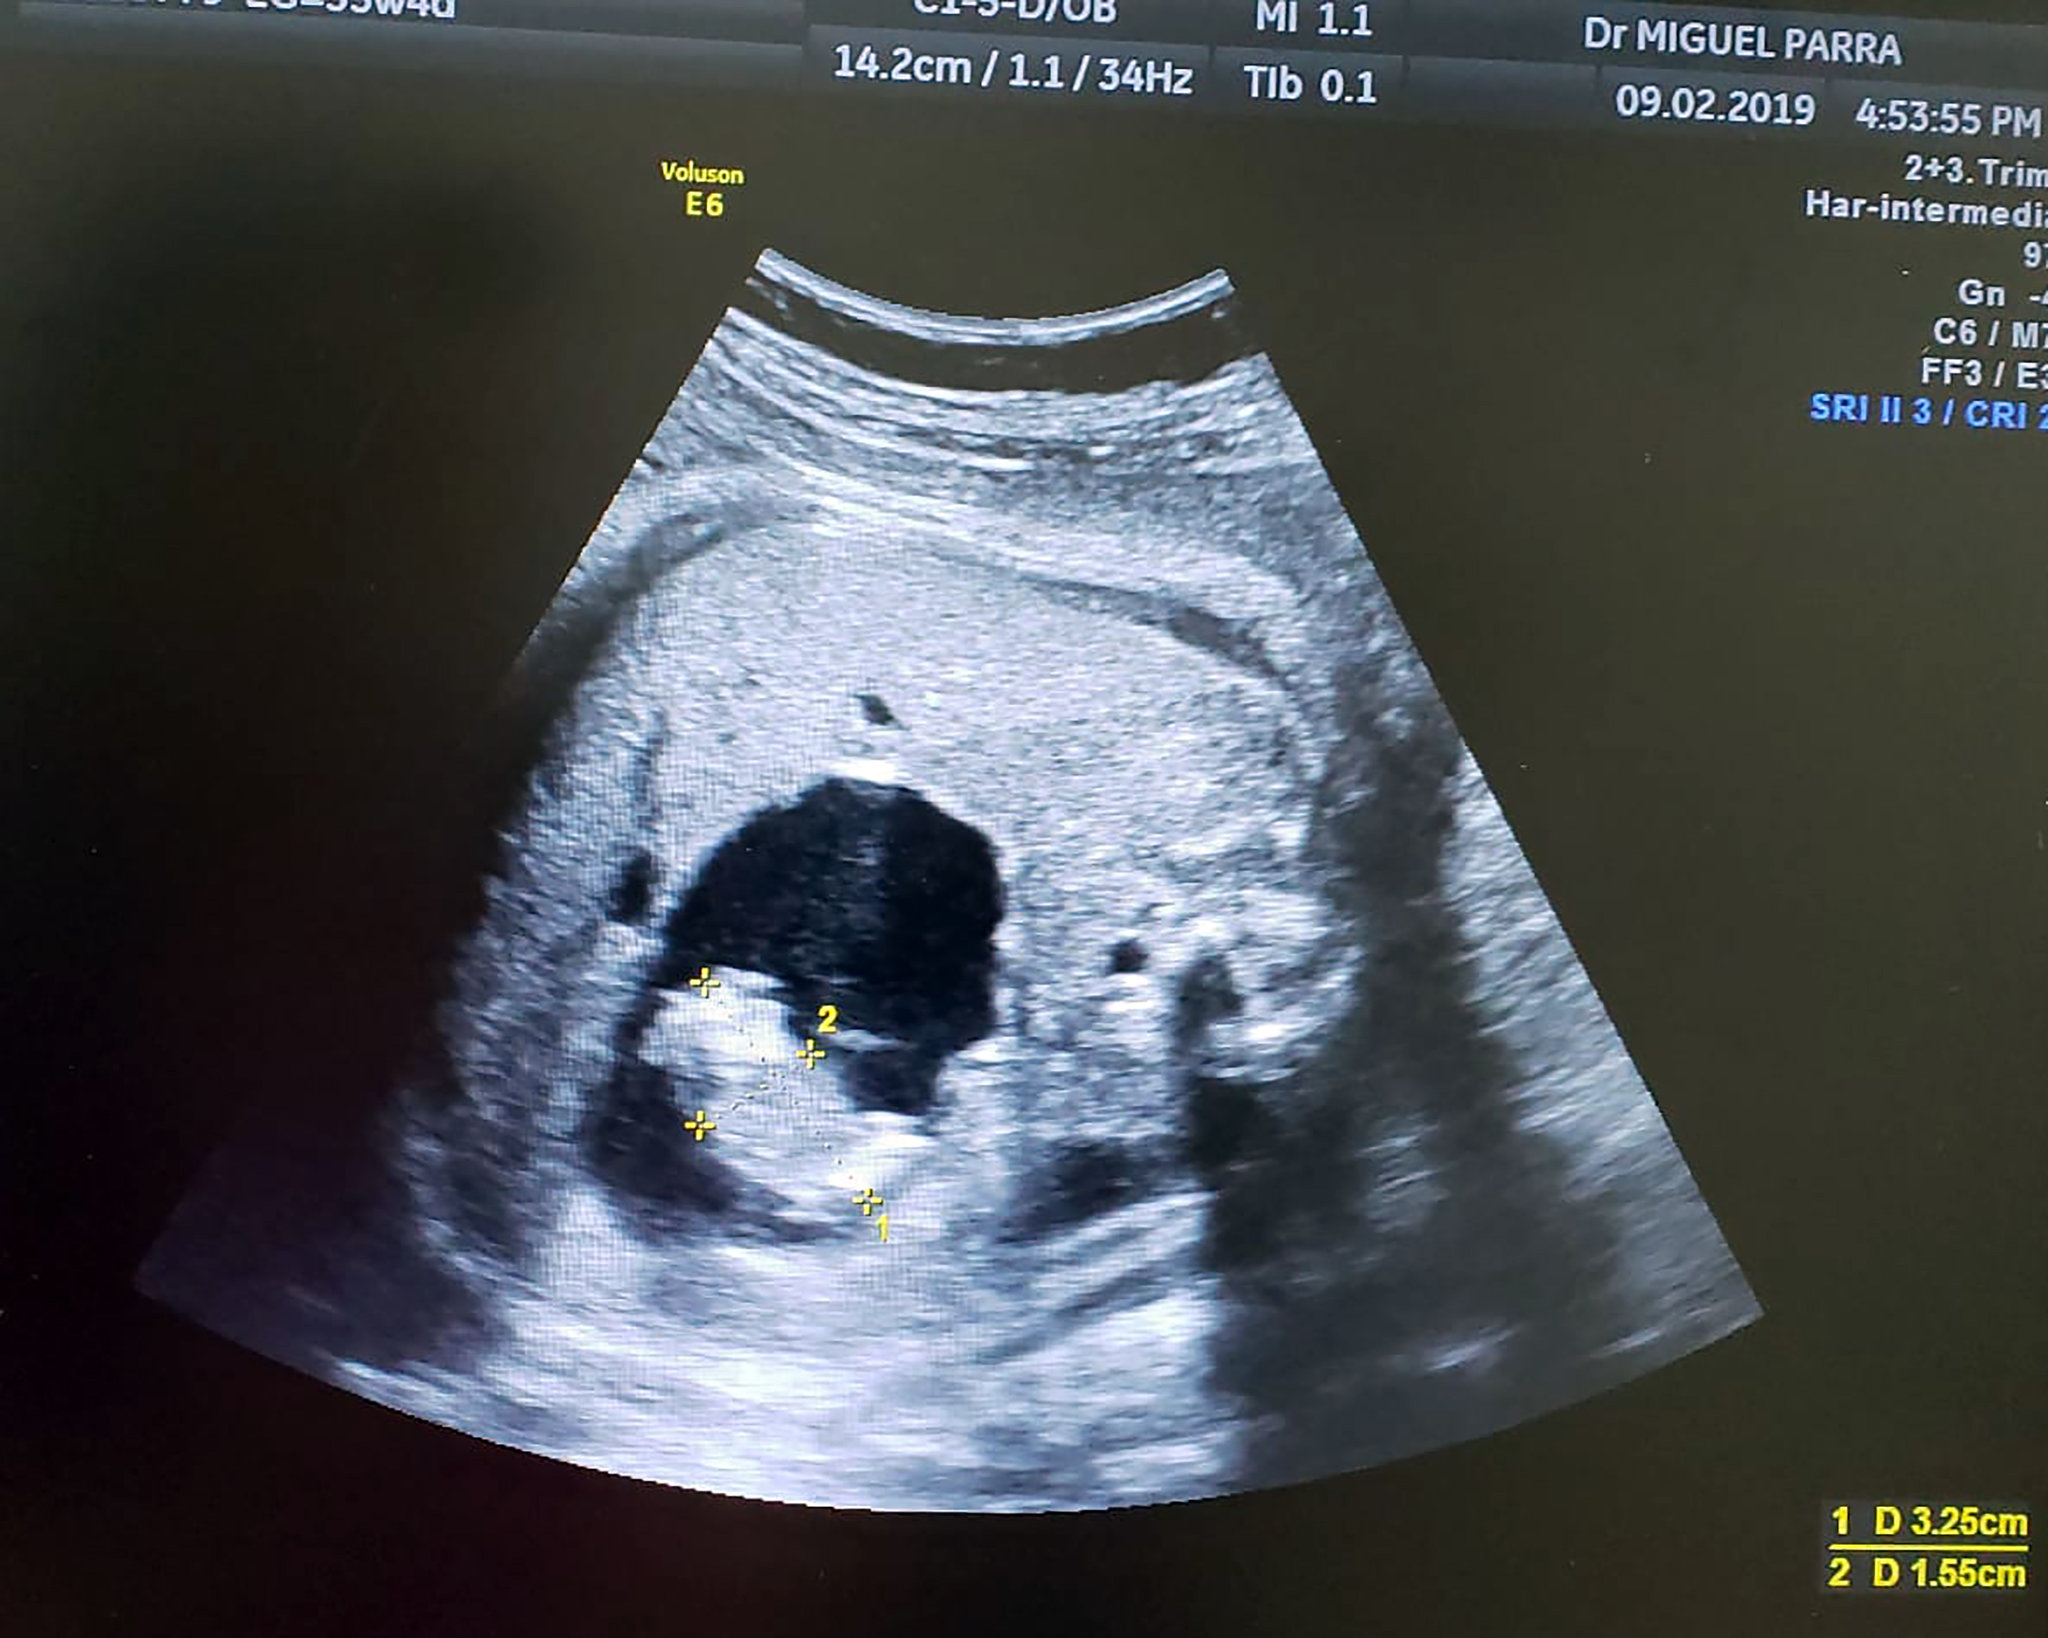

سونوگرافی واژینال (ترانسواژینال): بهترین روش برای اینکه جنین دوقلو در چند هفته مشخص میشود. در هفته ۶ تا ۸ بارداری، دو کیسه جنینی یا دو ضربان قلب جداگانه قابل مشاهده است. این روش دقیقترین پاسخ به جنین دوقلو در چند هفته مشخص میشود را میدهد.

سونوگرافی شکمی: معمولا از هفته ۱۰ تا ۱۲، جنین دوقلو در چند هفته مشخص میشود و دو جنین به وضوح دیده میشوند.

به طور خلاصه، جنین دوقلو در چند هفته مشخص میشود؟ پاسخ قطعی با سونوگرافی از هفته ۶ است. زودتر از این، جنین دوقلو در چند هفته مشخص میشود فقط به صورت احتمالی ممکن است.